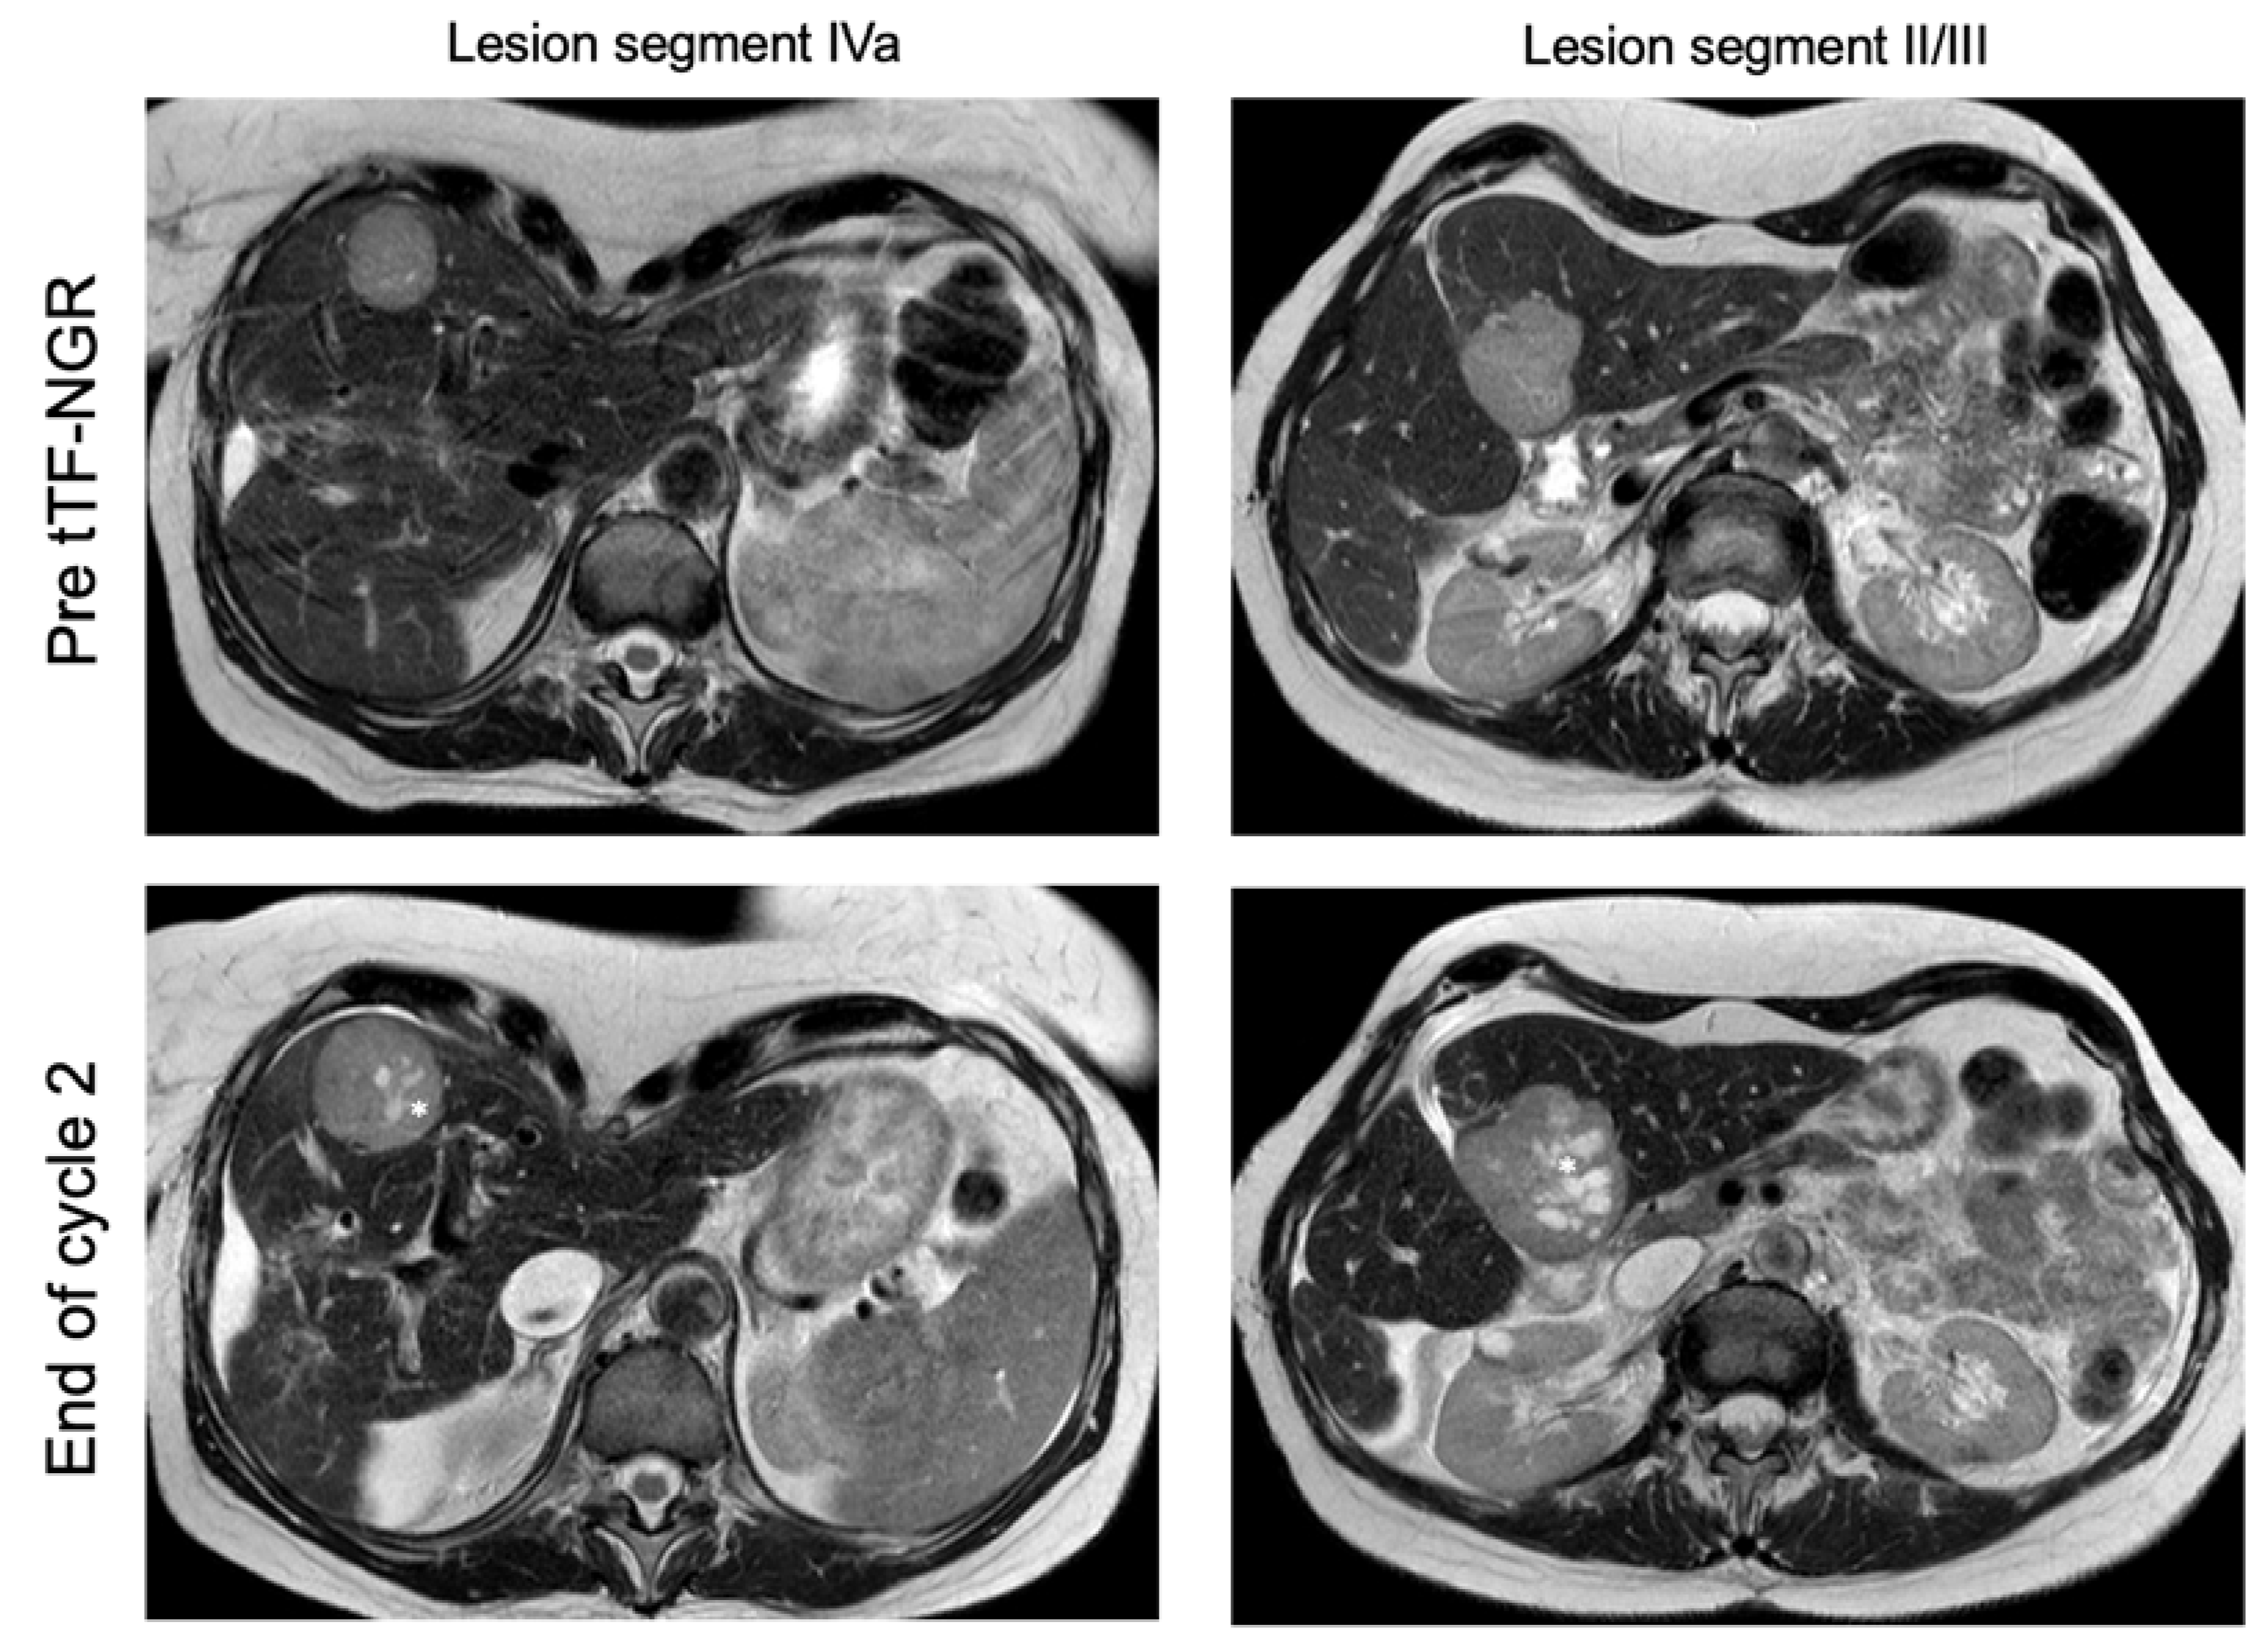

| 003 | m | 22 | metastatic non-seminomatous germ cell tumor | PEI, HD-PEI, surgery, TI, TIP, HD-CE, Gem/Ox, Radiation, Nivolumab | 2 | cycle 1: 1.0 cycle 2: 1.5 | good tolerability, no DLT | I: hemorrhagic/necrotic areas in liver lesions upon therapy (MRI) O: RECIST PD; Q: n.c. |

| 022 | f | 56 | hepatocellular carcinoma, metastatic | TACE, SIRT, Sorafenib (toxicity), Nivolumab (toxicity) | 2 | cycle 1: 3.0 cycle 2: 3.0 | good tolerability | I: hemorrhagic/necrotic areas in liver lesions upon therapy (MRI) O: RECIST PD; Q: n.c. |